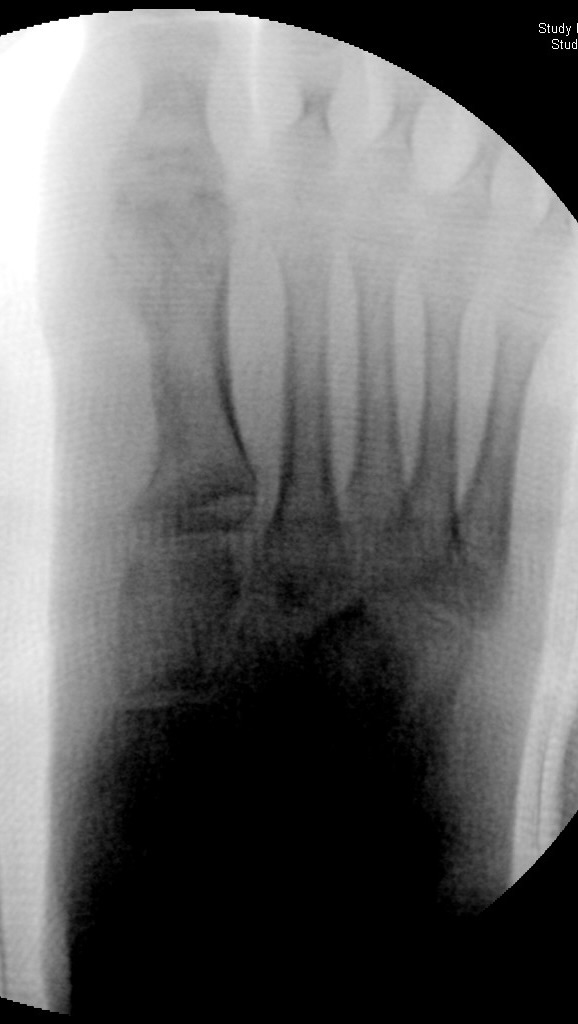

DMMO/DMDO (Distale Minimalinvasive Metatarsale Osteotomie/Distale Minimalinvasive Diaphysäre Osteotomie)

Die Indikation für eine DMMO oder DMDO (Distale Minimalinvasive Metatarsale Osteotomie/Distale Minimalinvasive Diaphysäre Osteotomie) beim Kind mit wachsendem Skelett ist nicht die klassische Metatarsalgie des Erwachsenen. In der Kinderorthopädie kann eine gute Indikation für die DMMO oder für eine DMDO der Ballen-Hohl-Fuß mit Metatarsalgie sein. Wird z. B. bei einer frühen Hohlfußkorrektur das Metatarsale I für eine bessere Rückfußeinstellung extendiert und zur Aufhebung der Extensorensubstitution die Sehne des M. tibialis posterior transferiert, kann sich im Verlauf eine Dysbalance der Metatarsalia entwickeln und eine Metatarsalgie unter II-IV auftreten. Mit einer DMDO werden die Köpfchen II-IV effektiv angehoben und die Beschwerden gebessert (Abb. 17 und 18).

Abb. 18 a-b: Beispiel einer DMDO beim Hohlfuß d.p. (dorso-plantare) Ansicht (a) und schräge Ansicht (b).